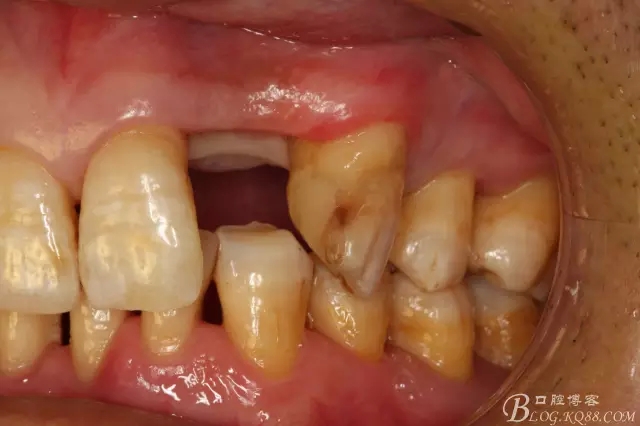

圖4.左側(cè)側(cè)面觀,22間隙正常,23近中輕度扭轉(zhuǎn)